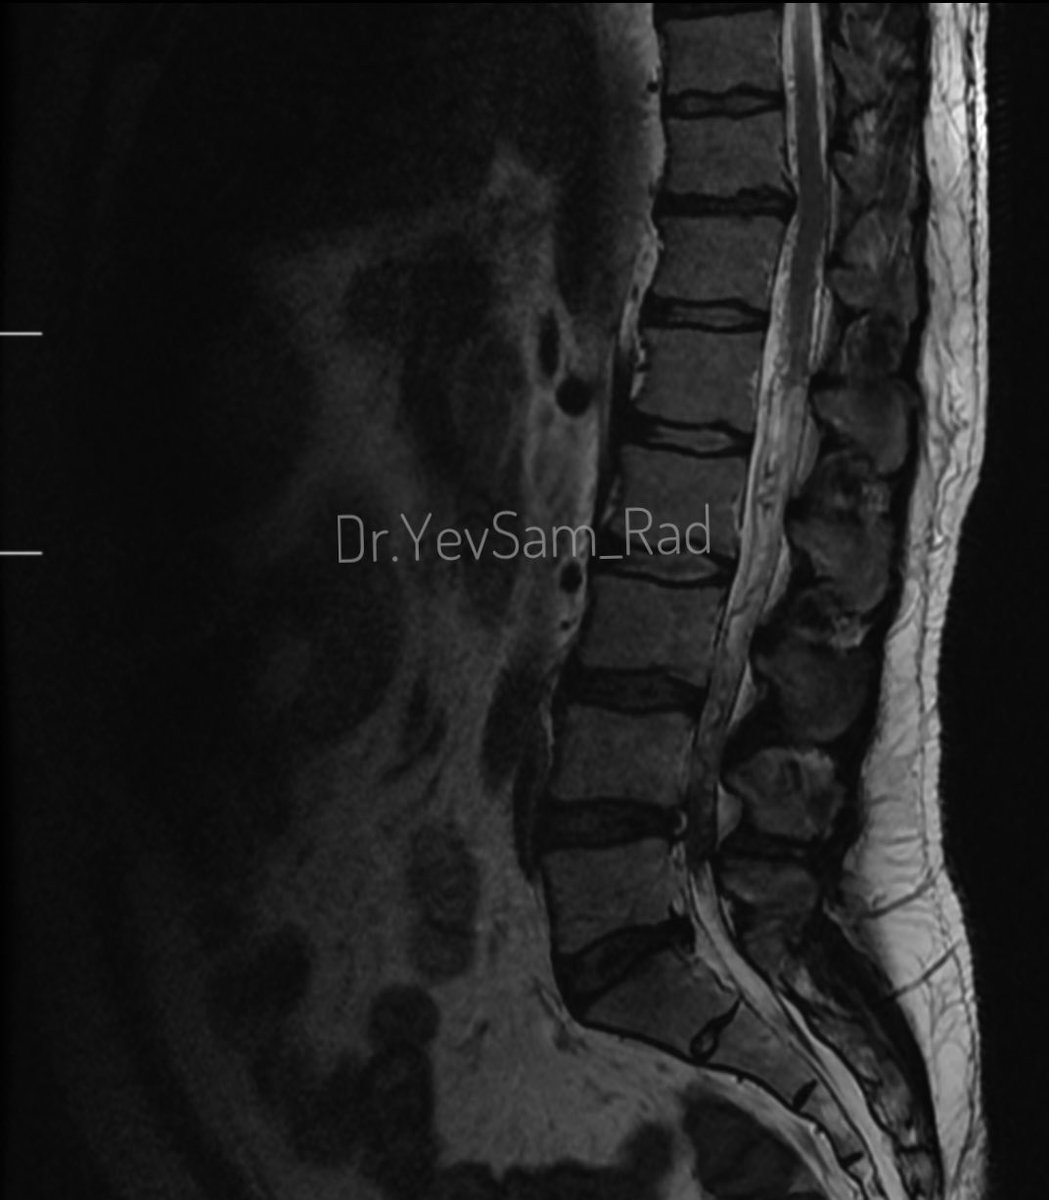

Young gentleman came with severe low back ache following an episode of dengue fever. What do we see here? #spineimaging #medtwitter #radtwitter #FOAMrad #neuroimaging @drvenkimdrd

DrYevSam_Rad's tweet image. Young gentleman came with severe low back ache following an episode of dengue fever. What do we see here?